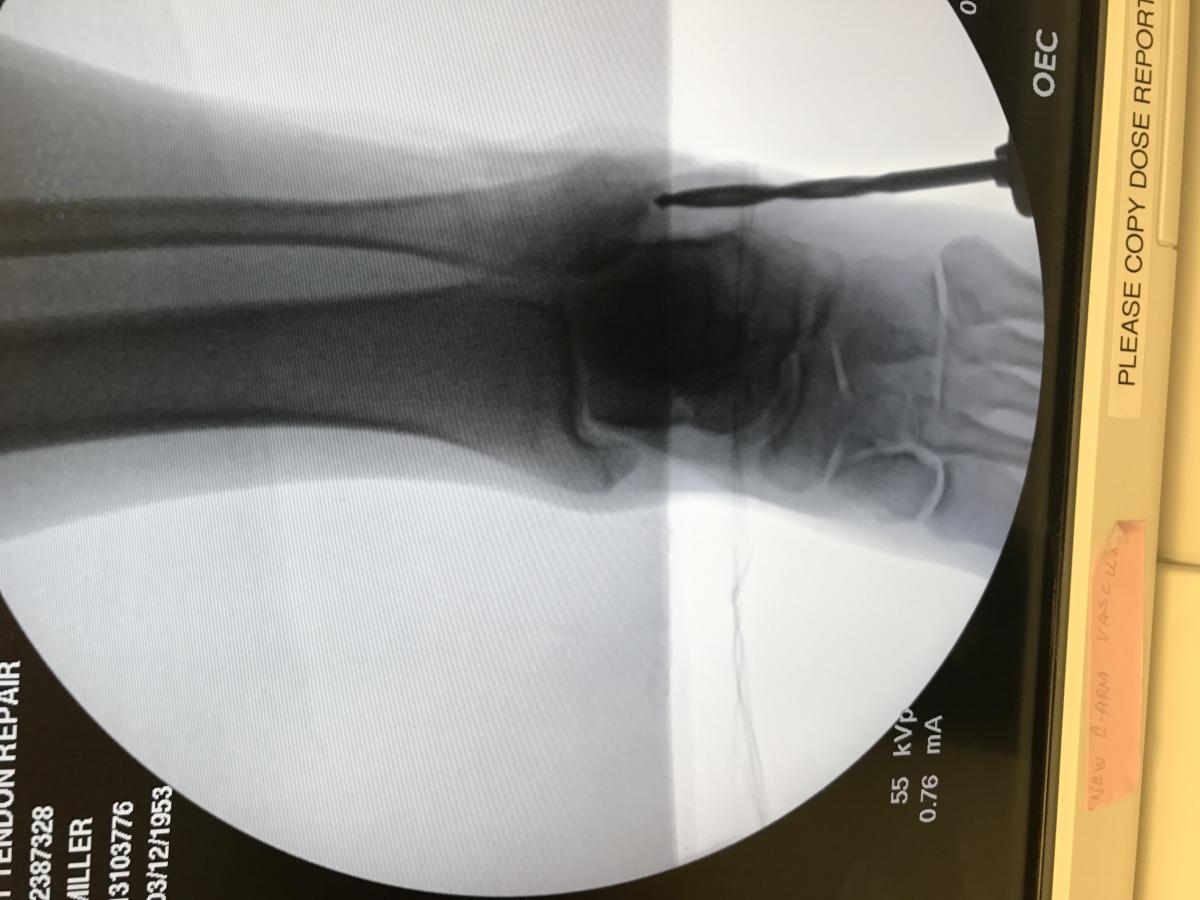

Next, inspect and deepen the retromalleolar groove. With the tendons retracted, make a sharp periosteal incision at the tip of the fibula and insert a 4.0 to 5.5 mm solid drill into the fibula under fluoroscopic guidance. Then ream the distal 2 to 3.5 cm of the fibular just deep to the desired groove. Use a rounded or blunted end of a bone tamp to gently impact and deepen the posterior aspect of the fibula approximately 6 to 8 mm to prevent dislocation. Take care not to fracture the area, which may require multiple light taps in the same area. The surgeon should avoid “dimple fracturing” the area. We prefer to invaginate the area smoothly and evenly so as to leave the area free of osseous ridges that may impinge or abrade the peroneals.